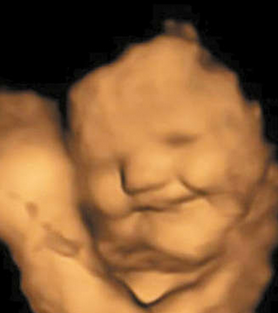

இன்னும் 35 கர்ப்பிணி பெண்களுக்கு காலே என்று அழைக்கப்படுகிற பரட்டைக்கீரை பவுடரைக் கொண்ட கேப்சுல்களை கொடுத்து விழுங்கச் சொன்னார்கள். 20 நிமிடங்கள் கழித்து அந்த கர்ப்பிணி பெண்களுக்கு ‘அல்ட்ரா ஸ்கேன்’ எடுக்கப்பட்டது. அதில் கேரட் கேப்சூல் விழுங்கிய கர்ப்பிணிகளின் கருக்குழந்தைகள் புன்னகைப்பதையும், பரட்டைக்கீரை கேப்சூலை சாப்பிட்ட கர்ப்பிணிகளின் கருக்குழந்தைகள் சிணுங்கி அழுவதுபோல காணப்படுவதையும் கண்டுபிடித்தனர்.

அதாவது, கேரட் கருக்குழந்தைகளுக்கு பிடித்து, அவர்களைப் புன்னகைக்க வைத்திருக்கிறது. பரட்டைக்கீரை அவர்களை சிணுங்க வைத்திருக்கிறது. கவனியுங்கள். இதில் கருக்குழந்தைகள் எதையும் சாப்பிடவில்லை. அவர்களின் தாய்கள்தான் அவற்றை சாப்பிட்டு இருக்கிறார்கள். அதன் தாக்கம். அவர்களுக்குள் வந்திருக்கிறது. இதுபற்றி ஆராய்ச்சியாளரும், டர்ஹாம் பல்கலைக்கழகத்தின் கரு மற்றும் பிறந்த குழந்தை ஆராய்ச்சி ஆய்வகத்தின் தலைவருமான பெய்சா உஸ்துன் கூறுகையில், “கருக்குழந்தைகள் தாயின் கர்ப்பப்பையில் இருக்கிறபோது, தங்கள் தாய்மார்கள் சாப்பிடுகிற உணவுகளின் சுவைகளுக்கு எதிர்வினையாற்றுகின்றன என்பதற்கான முதல் நேரடி ஆதாரத்தை நாங்கள் காட்டி இருக்கிறோம்” என தெரிவித்தார். இதுபற்றி ஆராய்ச்சியாளர்கள் மேலும் கூறும்போது, “கேரட் சுவை வெளிப்படும்போது கருக்குழந்தைகள் சிரிப்பு முகம் காட்டவும், பரட்டைக்கீரை சுவை வெளிப்படும்போது, அவை சிணுங்கும் அழுகை முகம் காட்டவும் அதிக வாய்ப்பு உள்ளது.